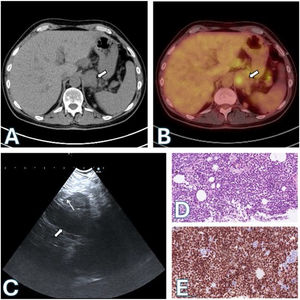

CT and PET scans revealed a pulmonary mass measuring 45mm×32mm with a Standard Uptake Volume (SUV) of 7.55. Additionally, bilateral pulmonary nodules, mediastinal lymph nodes (4R: SUV 2.24), and liver and bilateral adrenal lesions (left: 23mm, SUV 3.67) were identified.

An echobronchoscopy (EBUS) was then performed, puncturing 4R and 11R. The procedure was followed by echoendoscopy through the esophagus with the same echobronchoscope (EUS-B) (EB19-J10U, Pentax). A transgastric fine-needle aspiration (FNA) (SonoTip EBUS Pro Flex, Medi-Globe) was performed on a left adrenal mass.

Small to medium-sized atypical cells were found in the pathologic anatomy of the adrenal gland, which were compatible with melanoma metastasis. The cells showed dual positive staining for SOX-10/Melan A. A molecular oncology test confirmed the presence of a BRAFV600E mutation. A similar finding was observed in 4R, while 11R was negative for malignancy (Fig. 1).